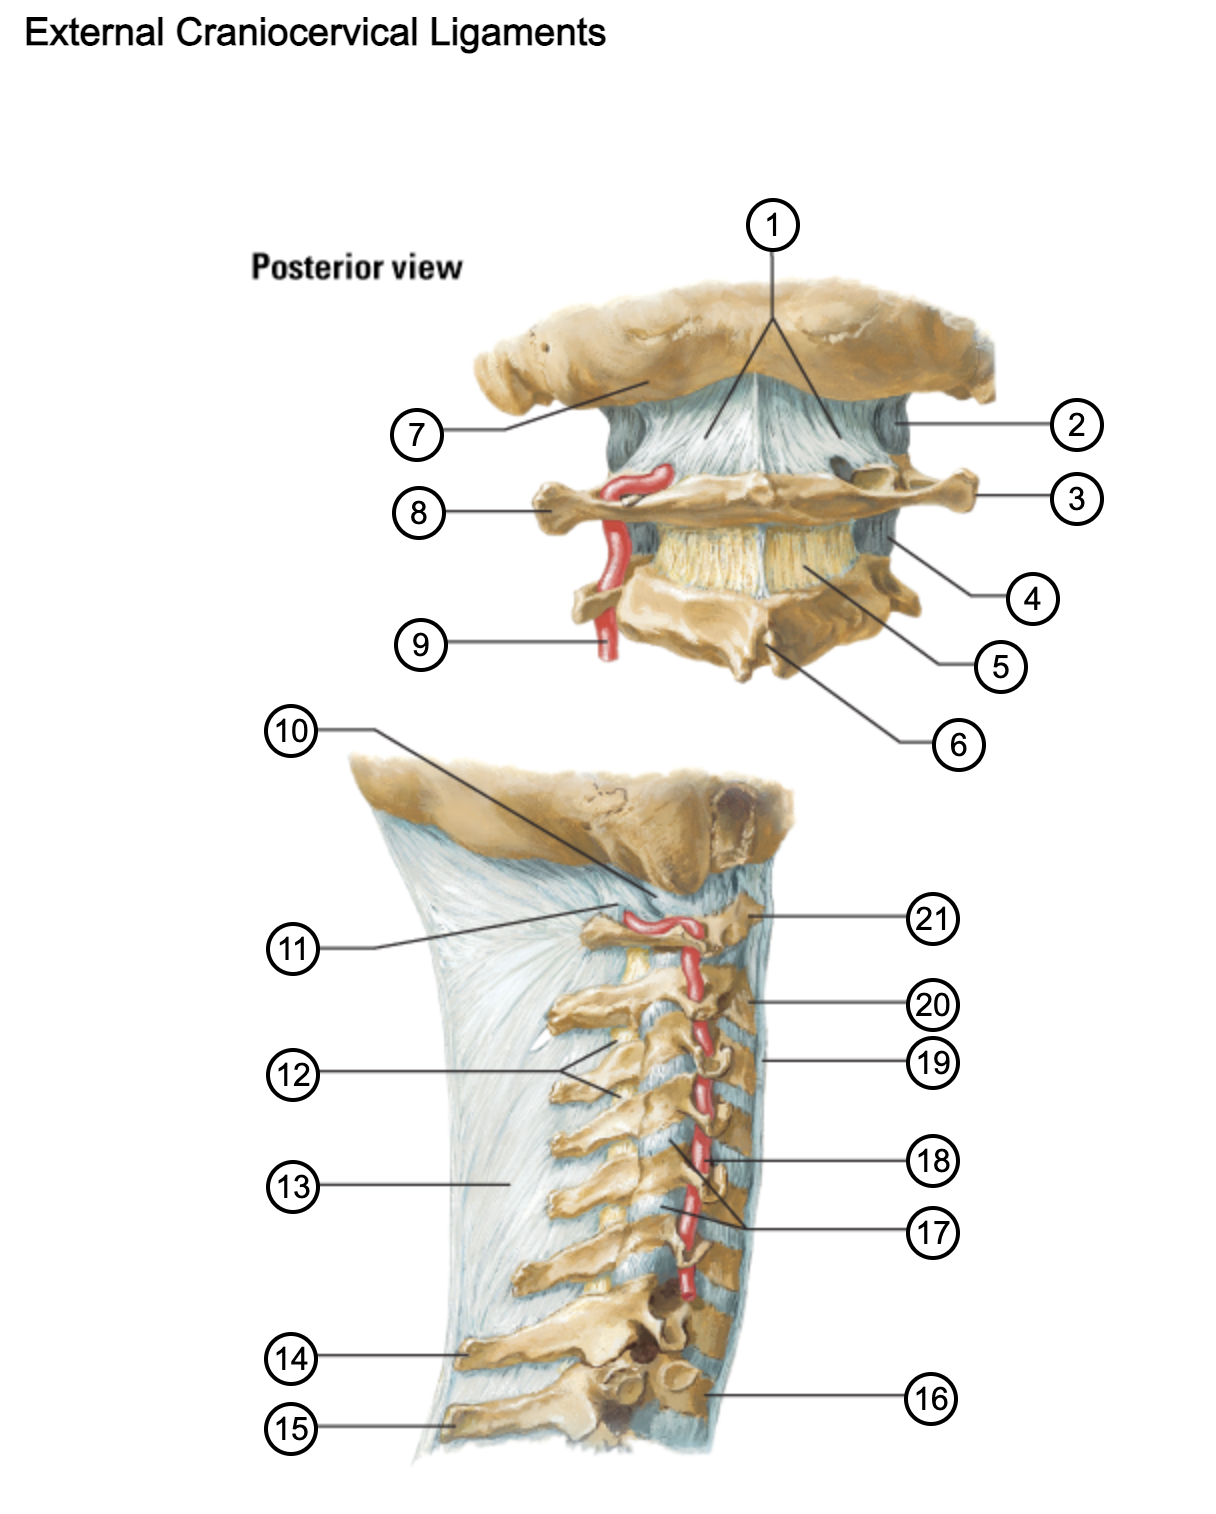

1

posterior antlantooccipital membrane

2

capsule of atlantooccipital joint

3

transverse process of atlas (C1)

4

capsule of lateral atlantoaxial joint

5

ligamenta flava

6

spinous process

7

occipital bone

8

transverse process of atlas (C1)

9

vertebral artery

10

capsule of atlantooccipital membrane

11

posterior atlantooccipital membrane

12

ligamenta flava

13

nuchal ligament

14

spinous process of C7 vertebra

15

spinous process of T1 vertebra

16

T1 vertebra

17

zygapophysical joints (C4-5 and C5-6)

18

vertebral artery

19

anterior longitudinal ligament

20

body of axis

21

Atlas (C1)